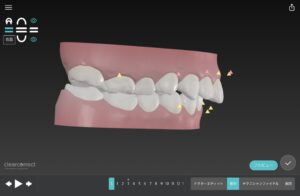

🔶初診時🔶

正面

でっ歯さん

噛むと噛み合わせ深く上の前歯で下の歯が見えない かがい咬合

英語でディープバイト

歯並びガタガタの

そうせい を気にして

マウスピース矯正希望で来院